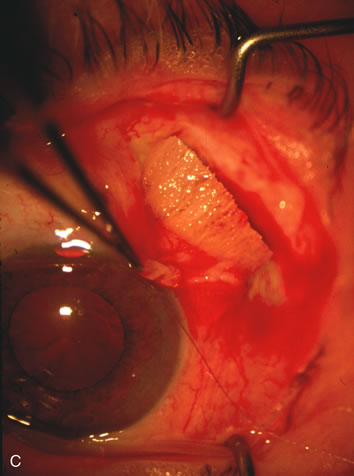

Fig. 7. Phacotrabeculectomy adjacent to a failed filter in cataractous eye. The ability to combine small-incision cataract extraction with trabeculectomy all through the same incision adjacent to the failed filter allows the surgeon to work in a familiar superior area. Avoiding incisions into the existing bleb decreases conjunctival buttonholes, hypotony, operating room time, and subconjunctival bleeding. A. Appearance of failed bleb with exposure of superior temporal quadrant gained with a corneal traction suture. B. Prepare a limbus-based conjunctival flap and a scleral flap. C. This bleb is at high risk to fail again justifying the need for MMC, 0.2 mg/cc applied on a pledget for 4 minutes. D. Insert the keratome and perform phacotrabeculectomy in the usual fashion.

Fig. 1. The anatomic advantage of small incision cataract surgery for the glaucoma patient. A. Long-term bleb function with a large cataract incision is difficult to achieve with either ECCE-trabeculectomy or trabeculectomy followed later by ECCE. This bleb failed to form sufficiently when combined with large incision ECCE. The inflammation, bleeding, and long-term wound healing with stimulation of fibroblasts associated with this technique are more likely to cause bleb failure. In addition, the increased iris manipulation necessary to deliver the nucleus and subsequent iris repair adds to the long-term breakdown of the blood aqueous barrier. B and C. Two-site phacotrabeculectomy has the advantage of small incision cataract surgery combined with separate site trabeculectomy. The incision size is one third the size of the standard ECCE. The inflammation is less severe, and cataract wound healing is confined to the temporal area. Visual rehabilitation with phacoemulsification and foldable IOL is much faster. Phacoemulsification allows successful lens extraction even in the unfriendly environment of a smaller pupil compared with ECCE. The trabeculectomy is performed in an entirely different site, well away from the wound healing associated with temporal phacoemulsification. The likelihood of this filter functioning long-term is greater than with ECCE-trabeculectomy. D. The surgeon also has the option of single-site phacotrabeculectomy with foldable IOL. Both the lens extraction and trabeculectomy are performed through one small 3.5-mm limbal incision.